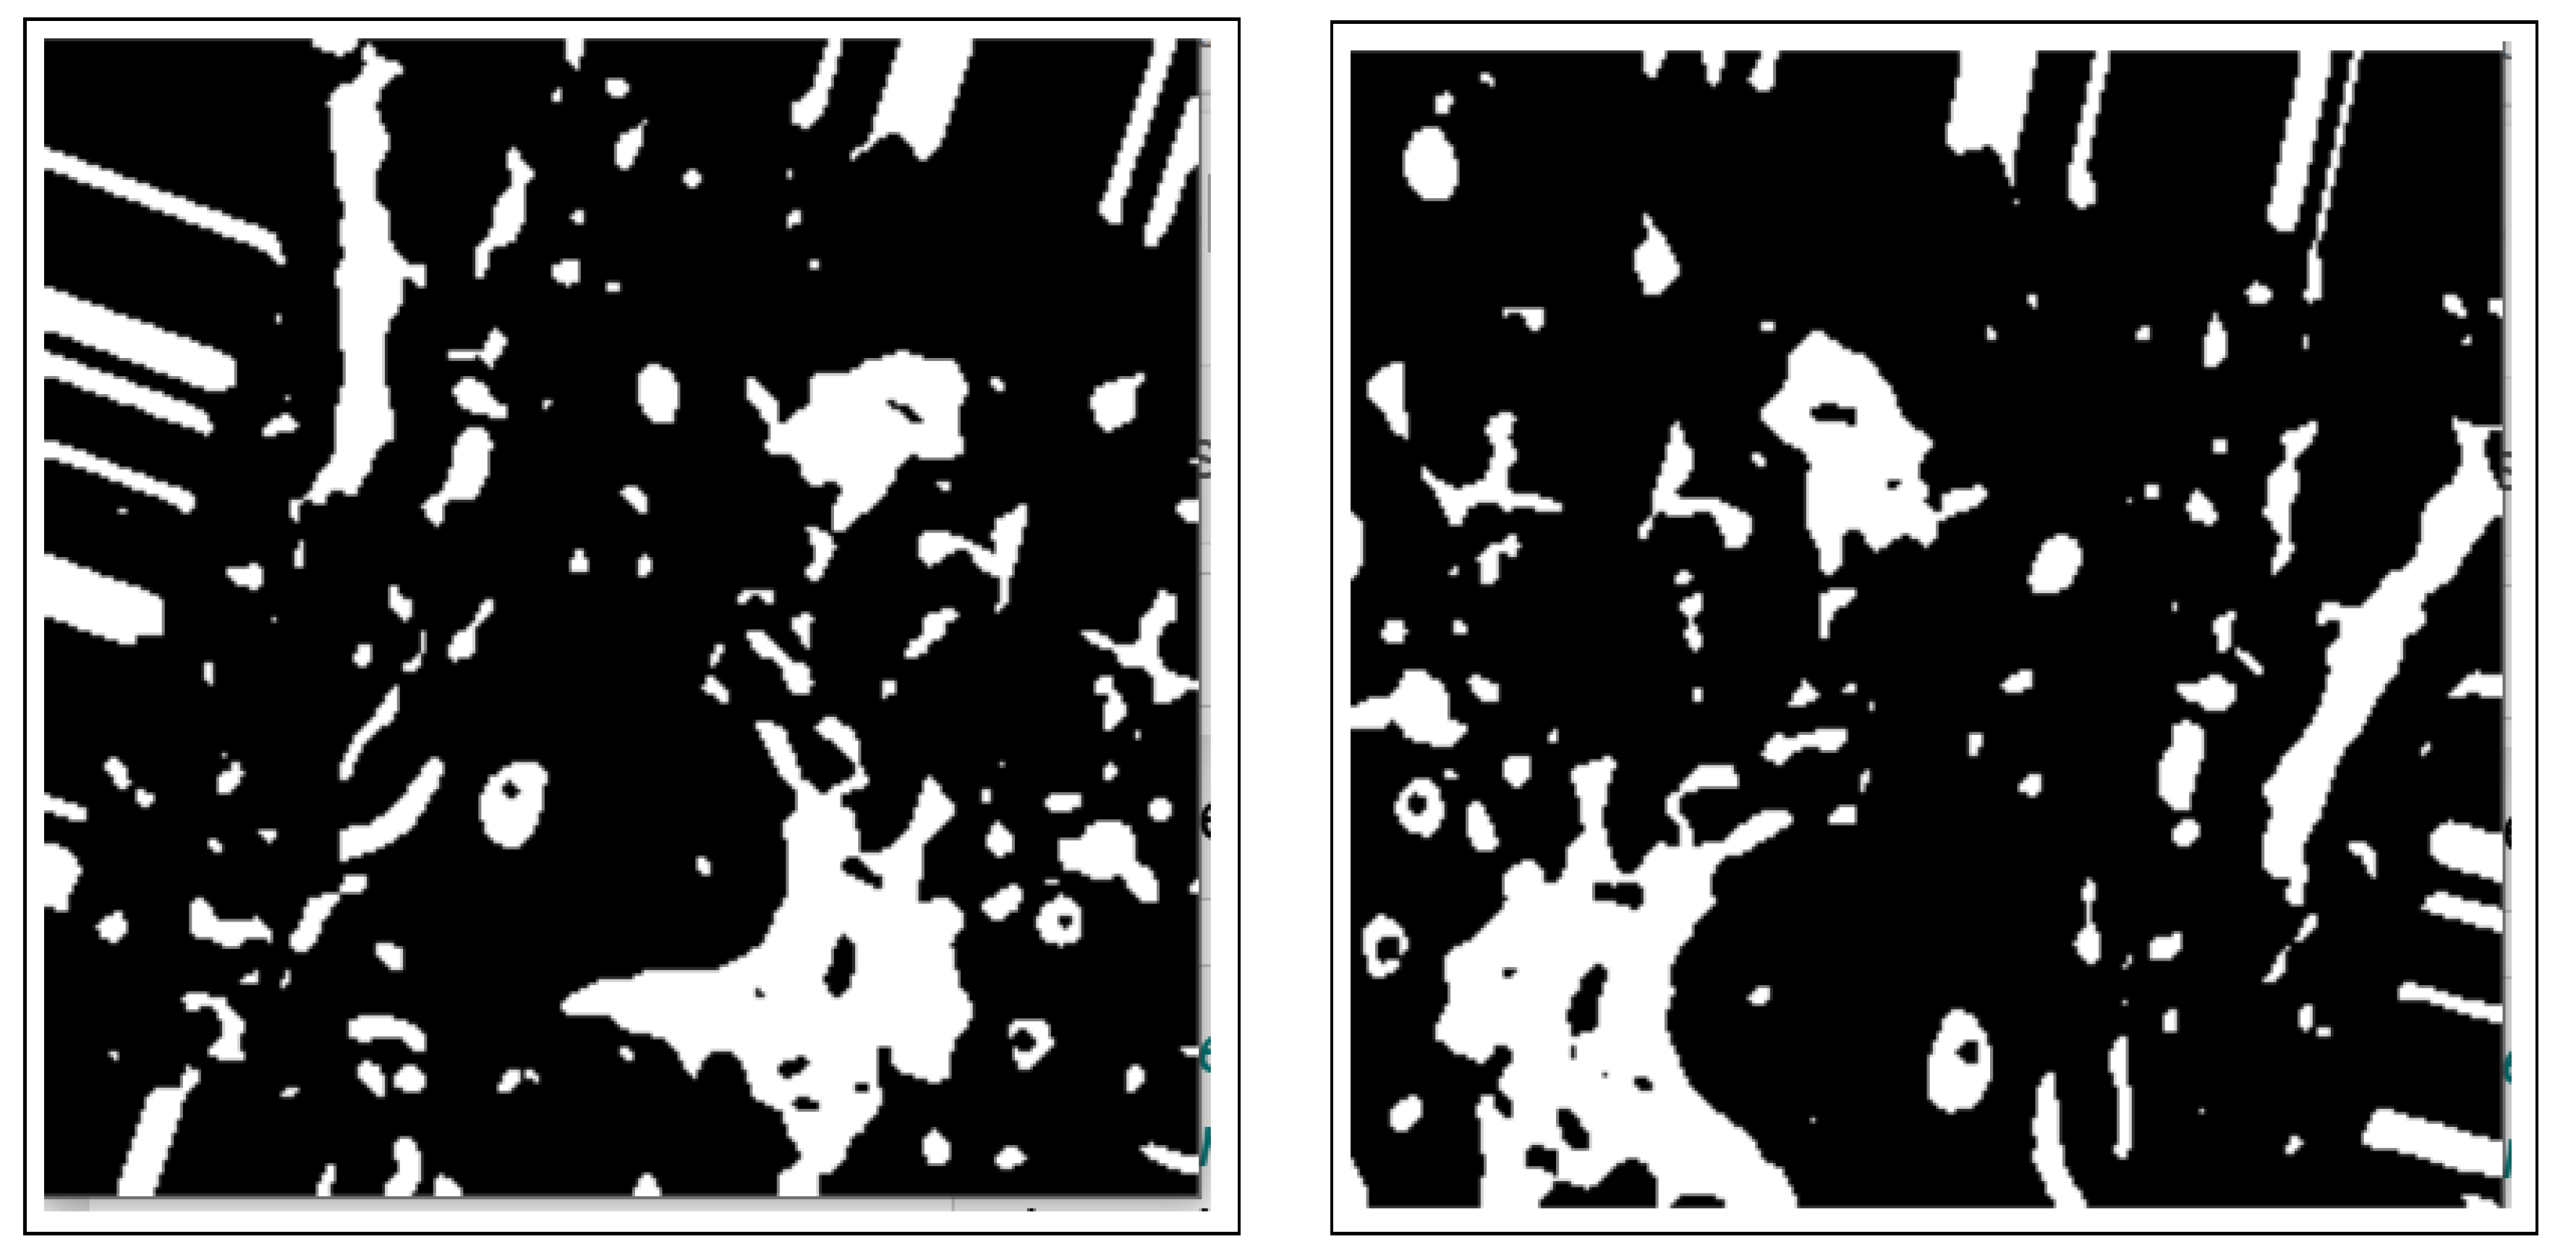

- The use of the connected component analysis method to group components with similar characteristics into binary masks that assist in separating overlapping and non-overlapping objects, thus avoiding over-segmentation.

- The binary masks from the connected component analysis method further aid in addressing the inaccurate segmentation of the image boundaries of intersecting objects, which is common with the active contours method. The proposed method clearly distinguishes the different ROIs from each other, clearly isolating and segmenting the cancerous lesions as visually documented in Section 3 and Section 4.

2.3.1. Connected Component Analysis